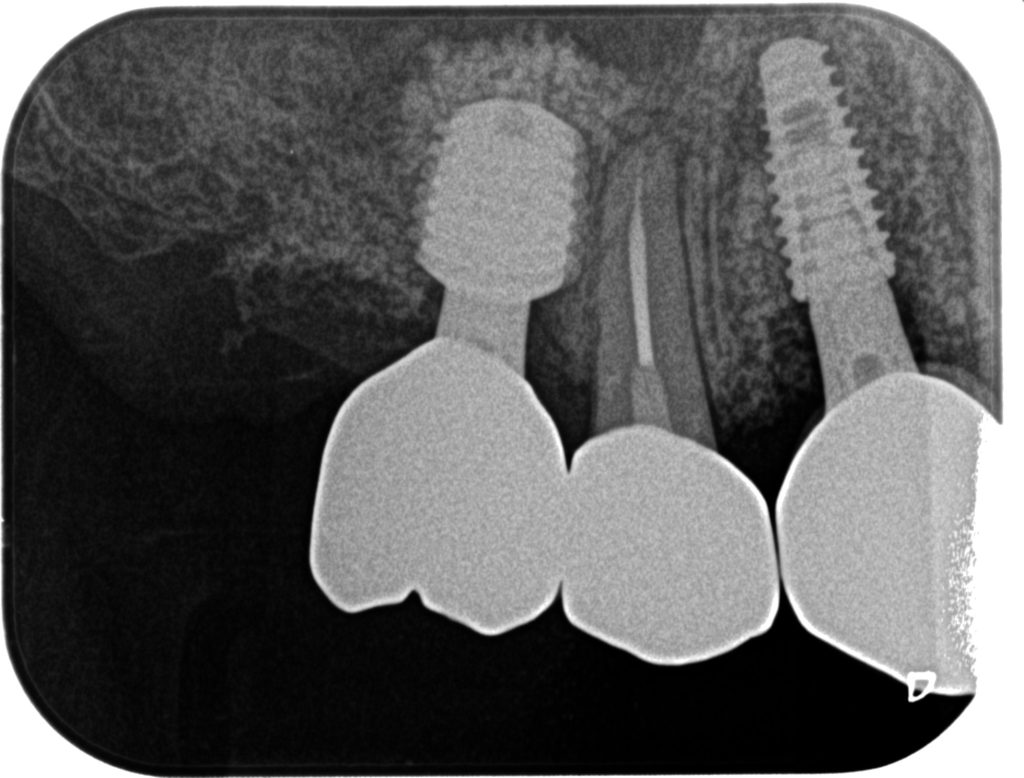

症例240代 女性 主訴 義歯が動いて煩わしい

治療前

治療後

入れ歯だと奥歯しっかり噛めず、取り外しも煩わしいので固定制のインプラントにして欲しいと訴え来院。

左右大臼歯部は、残存骨が1~2㎜程度で骨高が不足している為、ソケットリフト(上顎洞洞底膜挙上術)を行い、インプラントを埋入。口腔内全体で7本のインプラントを埋入。

約4ヶ月の治療期間を経て、全てジルコニアを装着し終了。

リスクとしては外科的侵襲がある。デメリットは、保険外診療の為、経済的負担がある。

費用 381万(税込)(オペ・仮歯・最終補綴物まで含む)